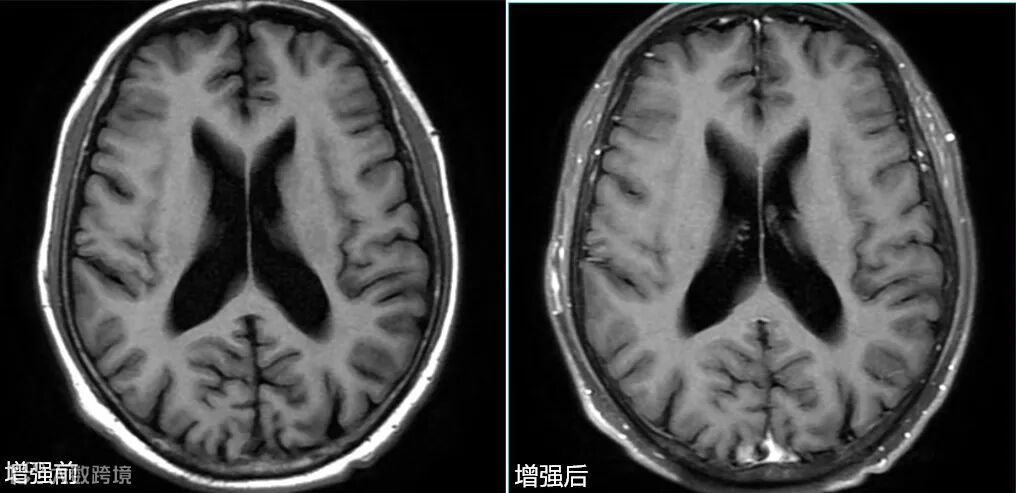

- 该序列可以做到增强前后同序列、同层面、同对比,如上图△。这也是很多医院坚持使用该序列增强的原因之一。